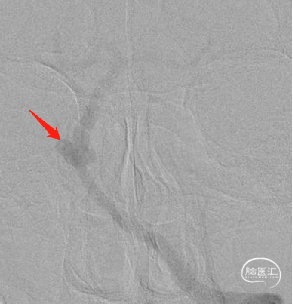

正侧位造影

3D旋转造影

通过3D工作位测量出基底动脉瘤瘤颈最宽处:6.5mm;载瘤动脉尺寸:近端直径3.7mm,远端直径4.2mm。